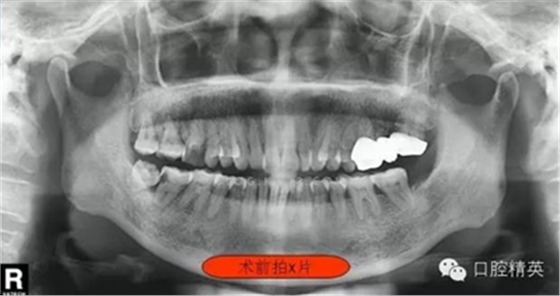

圖一

這位患者女性,年齡60歲。遠(yuǎn)中鄰面深齲,探診疼痛不適。主訴有夜間疼痛加重,叩診(+),一度松動,遠(yuǎn)中根部牙槽骨吸收,診斷牙髓炎。后來右下8拔除。